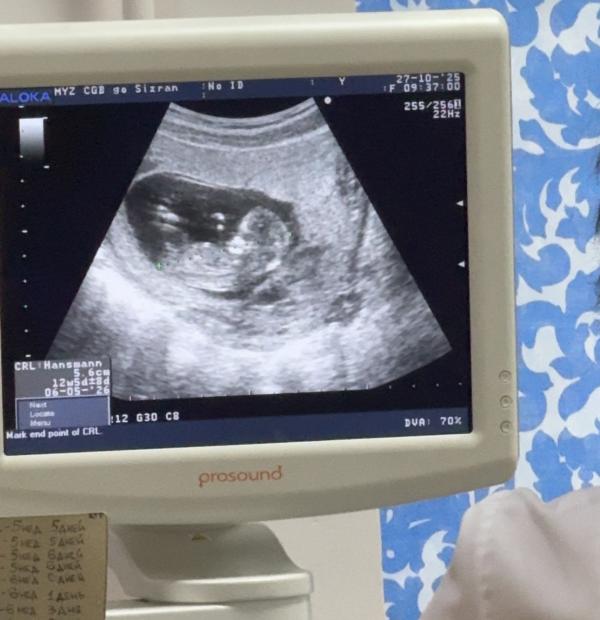

На 1 скрининге не факт, что скажут, д и не факт, что точно, а ждать 2 скрининга очень не хотелось. Я очень не терпеливая. И мы решаем сдать кровь на определение пола, к тому же через Сбер здоровье в гемотесте была скидка и анализ выходил всего лишь 3100 руб. Очень заманчиво. И вот 28.10 я сдаю кровь, а 29.10 в 19:40 приходит смс с результатами.